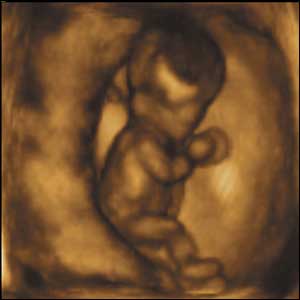

Eight weeks gestation, 40mm from crown to rump.

1 of 10

At eight weeks gestation, this foetus is able to kick and straighten his legs, turn them round and move his arms up and down.